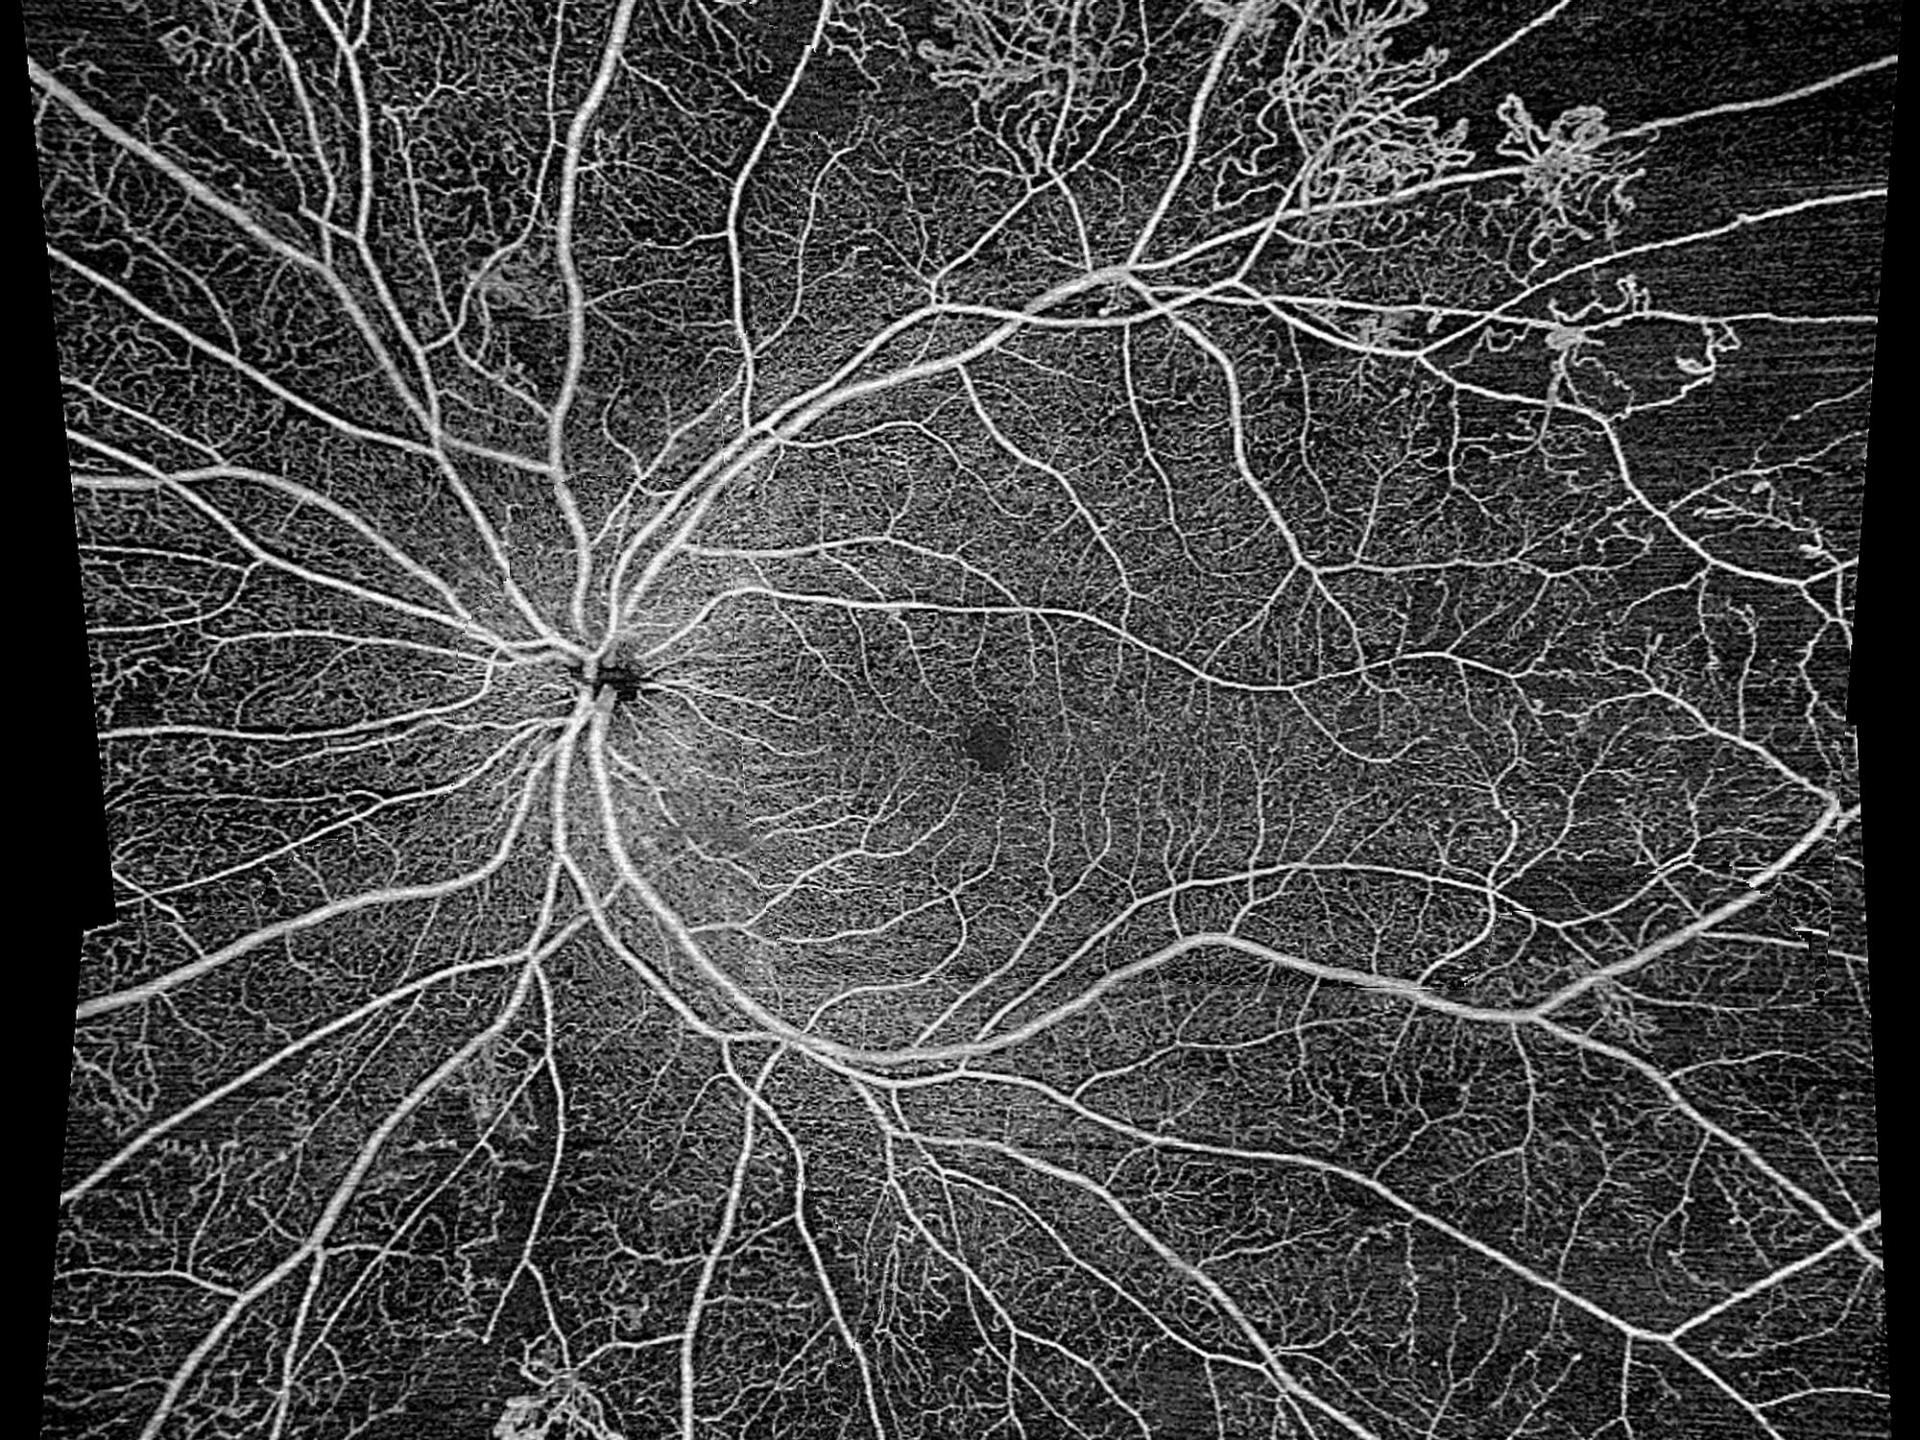

• Gain new insights into glaucoma and retinal conditions

Gain new insights into glaucoma and retinal conditions

Obtenha novos insights sobre glaucoma e condições retinianas

O AngioPlex Metrix para mácula e ONH permite a avaliação e acompanhamento de doenças oculares progressivas, como retinopatia diabética e glaucoma, por meio de ferramentas de quantificação.

• AngioPlex for ONH of an eye with advanced glaucoma

AngioPlex for ONH of an eye with advanced glaucoma highlighting late stage cupping and blood vessels at the lamina cribrosa level.